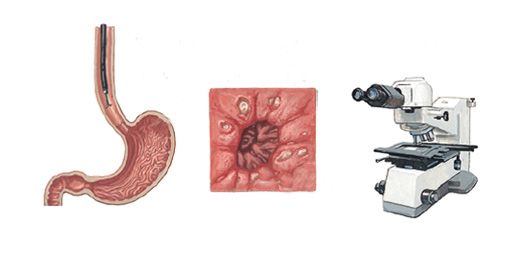

É um exame indicado para avaliação diagnóstica e tratamento das doenças da parte superior do tubo digestivo, incluindo o esôfago, o estômago e a porção inicial do duodeno.

Realizado introduzindo-se pela boca um aparelho flexível com iluminação central que permite a visualização de todo o trajeto examinado.

O exame é realizado com anestesia tópica (um spray de anestésico na garganta) e com sedação, utilizando medicação administrada por uma veia para permitir que você relaxe e adormeça.

Se necessário, pequenas amostras de tecido (biópsias) podem ser colhidas durante o exame para análise microscópica detalhada. Não se preocupe, não dói.

Na presença de lesões elevadas (pólipos), o médico poderá realizar, dependendo do caso, a retirada da lesão (polipectomia) durante o exame.